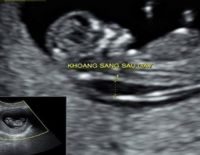

Độ mờ da gáy bình thường là bao nhiêu, tại sao phải đo?

Độ mờ da gáy bình thường là bao nhiêu, tại sao bác sĩ phải đo độ mờ da gáy là những kiến thức cơ bản bạn phải nắm vững. Đây là một thông số quan trọng giúp bác sĩ xác định xem bé có khỏe...